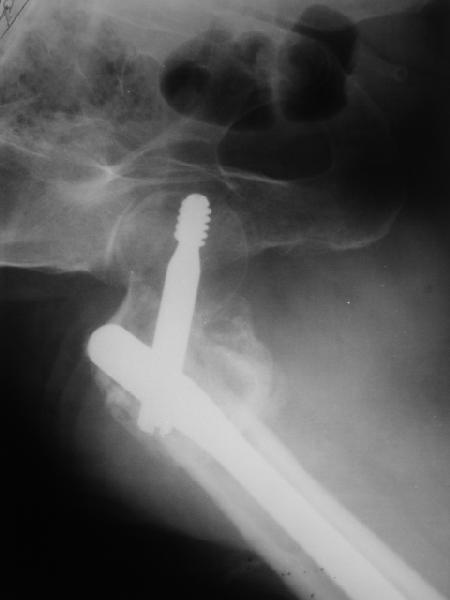

Возможно, пример (в приложении) поможет Вам определиться с выбором тактики лечения (у нашего пациента, кроме тугого ложного сустава вертельной области, сложная деформация н/3 бедренной кости; т.к. это не имеет значения к обсуждаемой теме - оставил "за кадром"). Как Вы видите, мы в данном случае не вводили чрескостные элементы в зону установки имплантата. При отказе от наложения опоры на таз (кстати, она не обязательно может быть громоздкая спицевая; арки со стержнями-шурупами, введенными в крыло подвздошной вполне достаточно) "не удивляйтесь", если опора со стержнями-шурупами, введенными в вертельной области в скором времени дестабилизируется, возникнет воспаление мягких тканей у чрескостных элементов. Такая опора "имеет на это право": нагрузка конечности от вершины дистального фрагмента до кончиков пальцев ляжет на нее. А двух-трех введенных рядом стержней-шурупов, как их не разноси от фронтальной плоскости, в данном

случае явно недостаточно для адекватной фиксации. + для того, чтобы выбрать оптимальные чрескостные элементы для промежуточной и дистальной опор, можете воспользоваться атласом